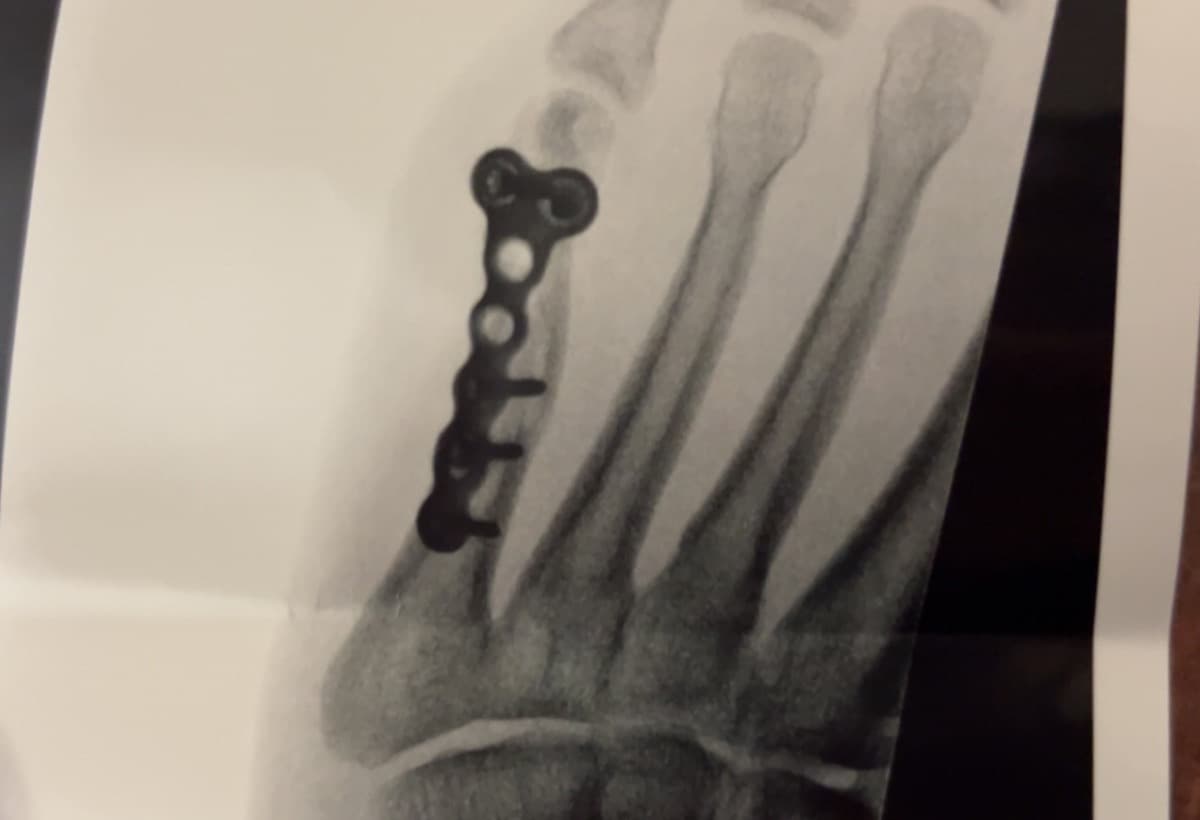

Our brother, Blake had an accident last week and broke his foot. He had to have surgery this morning. His foot was broken more than they could see, so they had to put in a full plate and screws. Blake is self employed, his fiancée babysits and takes care of their son. We are trying to rally around them, and help relieve the financial burden while he recovers, and has to be off work. If you could kindly donate, we would greatly appreciate it. Please pray for a speedy recovery with minimal pain. Thank you, and God Bless you all! With lots of love!!